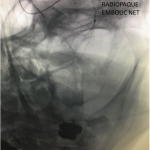

Figure 4.

Catheter angiography prior to angioplasty revealed critical stenosis (Figure 2). Angioplasty was therefore performed under local anesthesia with an embolic protection device deployed to catch any dislodged debris (Figure 3). After angioplasty, a stent was opened across the lesion to maintain long-term patency (Figure 4). Post-stent angiography showed smooth dilatation of the lesion. The patient’s aphasia continued to improve at his 6-week follow-up visit and duplex revealed no significant stenosis through the stent.